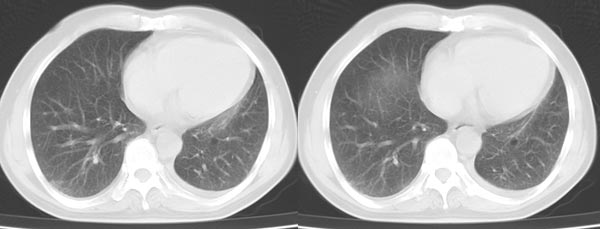

以下是引用dyqct在2006-4-1 22:20:00的发言:[br]左肺上叶明显萎陷、实变,支气管大部通畅,部分扩张,部分壁似见串珠状钙化。主动脉弓旁见肿大淋巴结。纵隔左移。左侧胸壁后缘见新月形高密度,边界清楚。[br] 考虑:1、左肺上叶肺不张伴支气管扩张(牵拉性),可能为支气管内膜结核所致。[br] 2、左侧少量胸腔积液。[br]

以下是引用piao001在2006-4-2 14:13:00的发言:[br]左肺上叶不全性不张,其内见钙化及扩张支气管,结合病史,考虑支气管内膜结核。建议支气管镜明确检查。